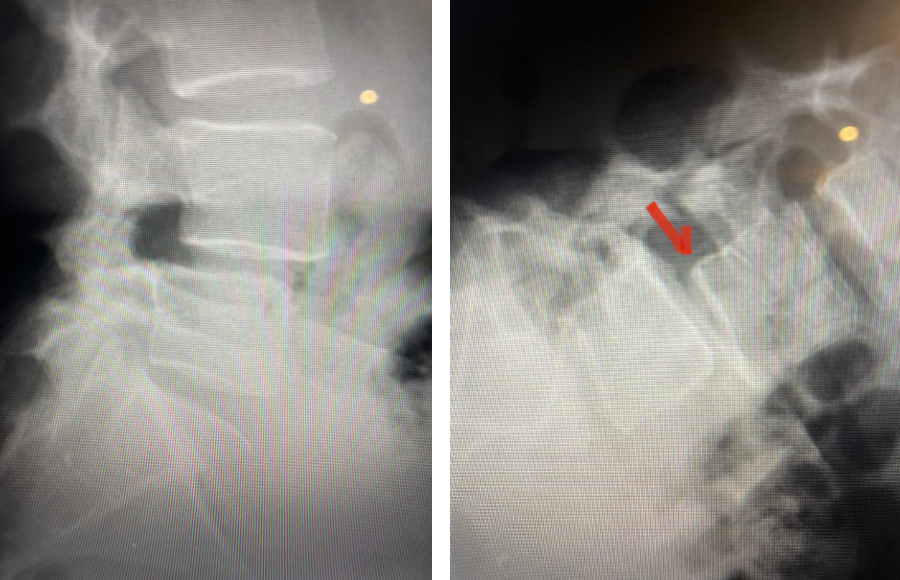

Here is a dramatic example of a patient who had prior laminectomy and fusion surgery four years earlier, and now presents with low back pain with severe burning pain in her right lower extremity pain. She did not respond to epidural steroids. She had a prior L3-S1 laminectomy, and an L3-5 instrumented fusion. A current MRI (Fig 4) demonstrated severe L2-3 next segment stenosis due the development of massively hypertrophied or enlarged L2-3 joint complexes. There was also a grade 1 retrolisthesis of L2 on L3 with a large anterior disc osteophyte complex. The configuration of the stenosis was worse in the right lateral recess secondary to the anterior osteophyte and more right-sided facet compression of the thecal sac, correlating with the patient’s right-sided symptoms. When the anatomy correlates with the patient’s symptoms that is the best set up for success. It was decided to offer a revision surgery to the patient, who agreed.

Fig 4: Sagittal and axial T2-weighted lumbar MRI images demonstrating severe next segment degeneration and stenosis at L2-3 above prior L3-5 fusion. Note retrolisthesis and significant facet arthropathy at L2-3 (red arrow).